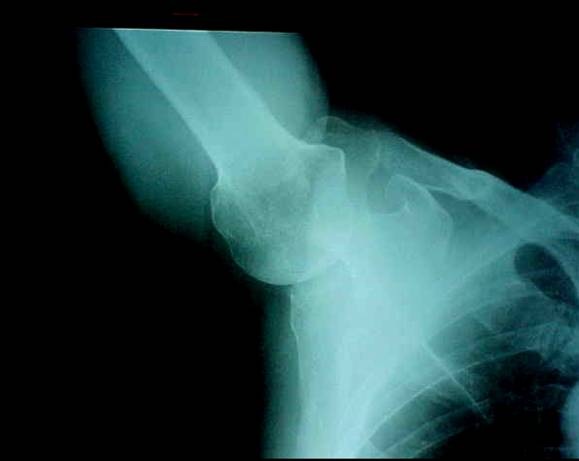

RX No. 5: Axilar